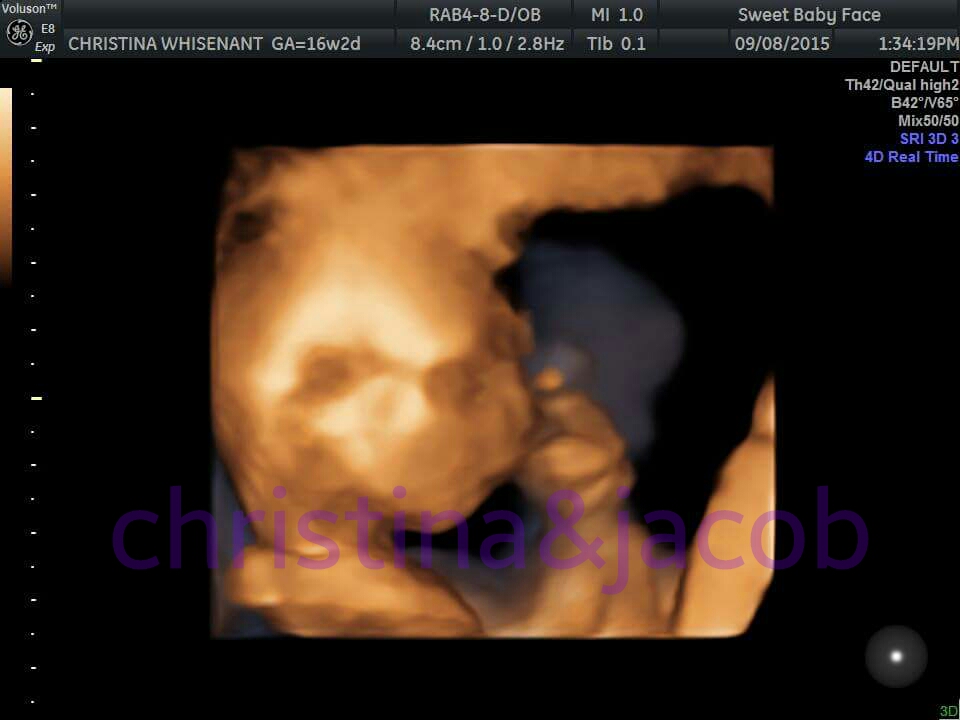

@blumartyr The office I went into offers a "gender determination scan" for non-patients since I'm using a Midwife (what they called it) as early as 15 weeks. I went in a little past 16 weeks and was told mine. Best to you and yours!